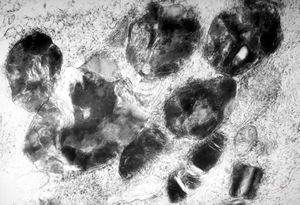

F, 24y. | molluscum contagiosum … virions

F, 24y. | molluscum contagiosum

F, 7y. | molluscum contagiosum … virions